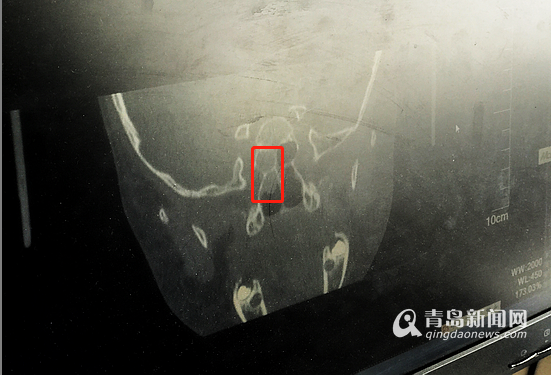

于海玲初步診斷發(fā)現(xiàn)在亮亮的鼻腔后端靠近顱底處有一個(gè)腫物,是鼻腔顱底占位,同時(shí)不排除腫瘤可能,需要盡快手術(shù)。

亮亮鼻腔后端靠近顱底處有一個(gè)腫物。